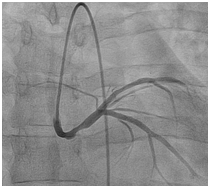

38 year old male patient with 15 packs per year smoking history presented to a peripheral hospital with acute onset typical chest pain for 30 minutes. His ECG revealed ST- Elevation acute lateral wall myocardial infarction. He was thrombolyzed with t-PA with complete resolution of his ECG changes. Echocardiogram showed mild LV dysfunction with LVEF of 45% and lateral wall hypo kinesis. He was then transferred to our center where he was taken to the catheterization laboratory and diagnostic coronary angiogram was done following obtaining an informed consent. It was difficult to engage the left coronary artery with Judking left catheter. A right judkins was taken to visualize the right coronary system. This revealed that the right coronary artery to be free of disease (Figure 1) and the left coronary artery to originate from the right coronary sinus. The anomalous left main showed a mid-shaft hazy and eccentric lesion (Figure 2), Normal left anterior descending and normal left circumflex. The patient was discussed in a heart team meeting and it was decided to obtain coronary CT angiogram to define the course of the anomalous left coronary artery which was retro-aortic (Figure 3). The patient was offered bypass surgery of which he declined to accept. The patient informed decision was to opt for PCI. A straight forward intervention was carried out using Judging’s 4 guiding catheter, which easily incubated the anomalous left main a BMW wire easily passed to the distal LAD and a direct 4.0x22 mm resolute stent deployed (Figure 4). A second stent 4.0x8 mm resolute stent deployed proximally to cover an area of plaque shift. A final IVUS was done which showed well stent apposition (Figure 5). The procedure was supplanted with 300mg of Plavix and 7000 unit of heparin. He was discharged next day.

Figure 4 Post stenting of anomalous left main.